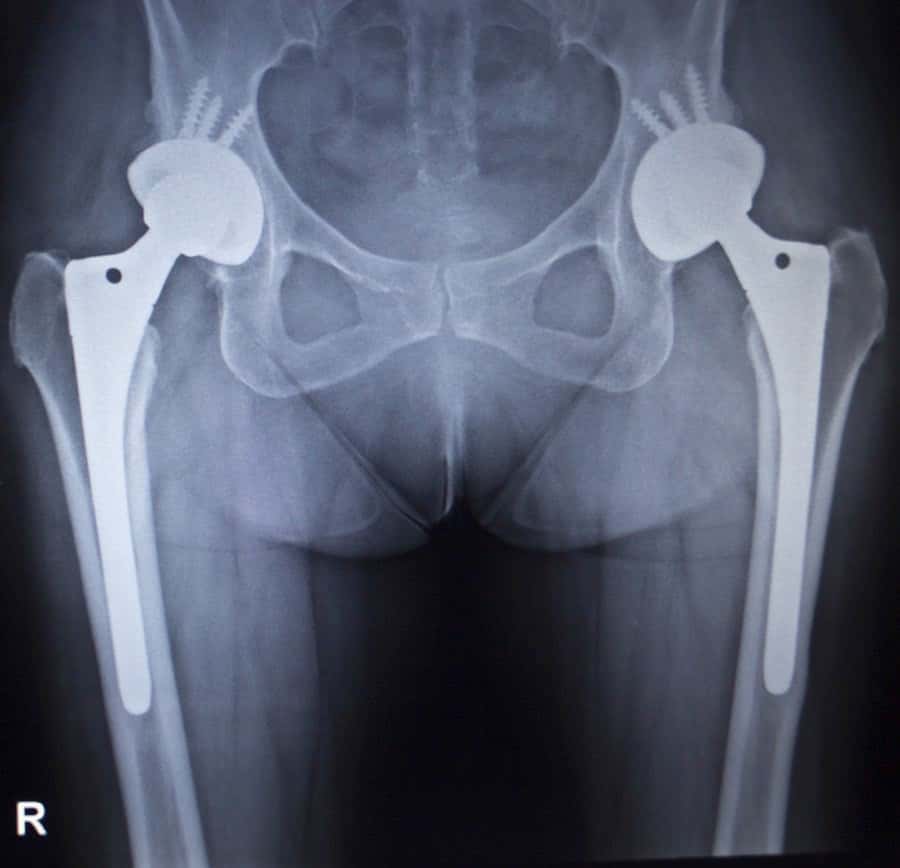

Do you take your bones for granted? Most of us do, unless we break one. If that happens, we often have to cope with a great deal of pain and inconvenience. If we break a leg or a hip it becomes far worse, especially for older people. The mortality rate after hip fracture ranges from 15 to 25% in the first year (New England Journal of Medicine, Nov. 1, 2007).